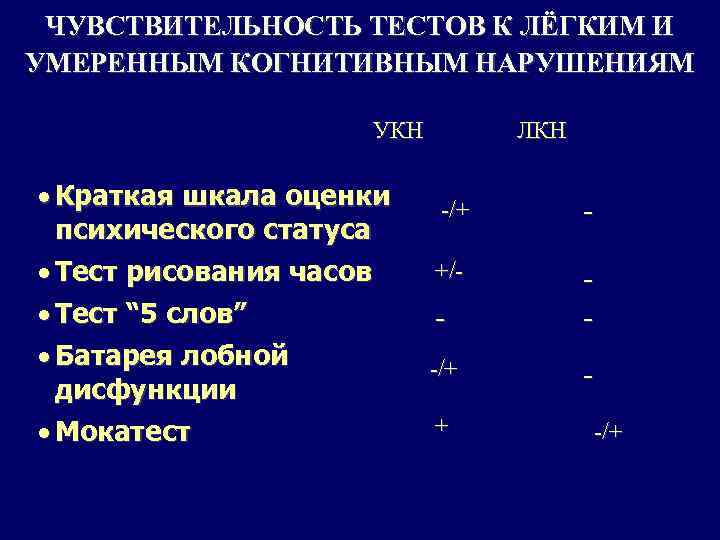

ЧУВСТВИТЕЛЬНОСТЬ ТЕСТОВ К ЛЁГКИМ И УМЕРЕННЫМ КОГНИТИВНЫМ НАРУШЕНИЯМ УКН · Краткая шкала оценки психического статуса · Тест рисования часов · Тест “ 5 слов” · Батарея лобной дисфункции · Мокатест ЛКН -/+ - +/- - - -/+ - + -/+